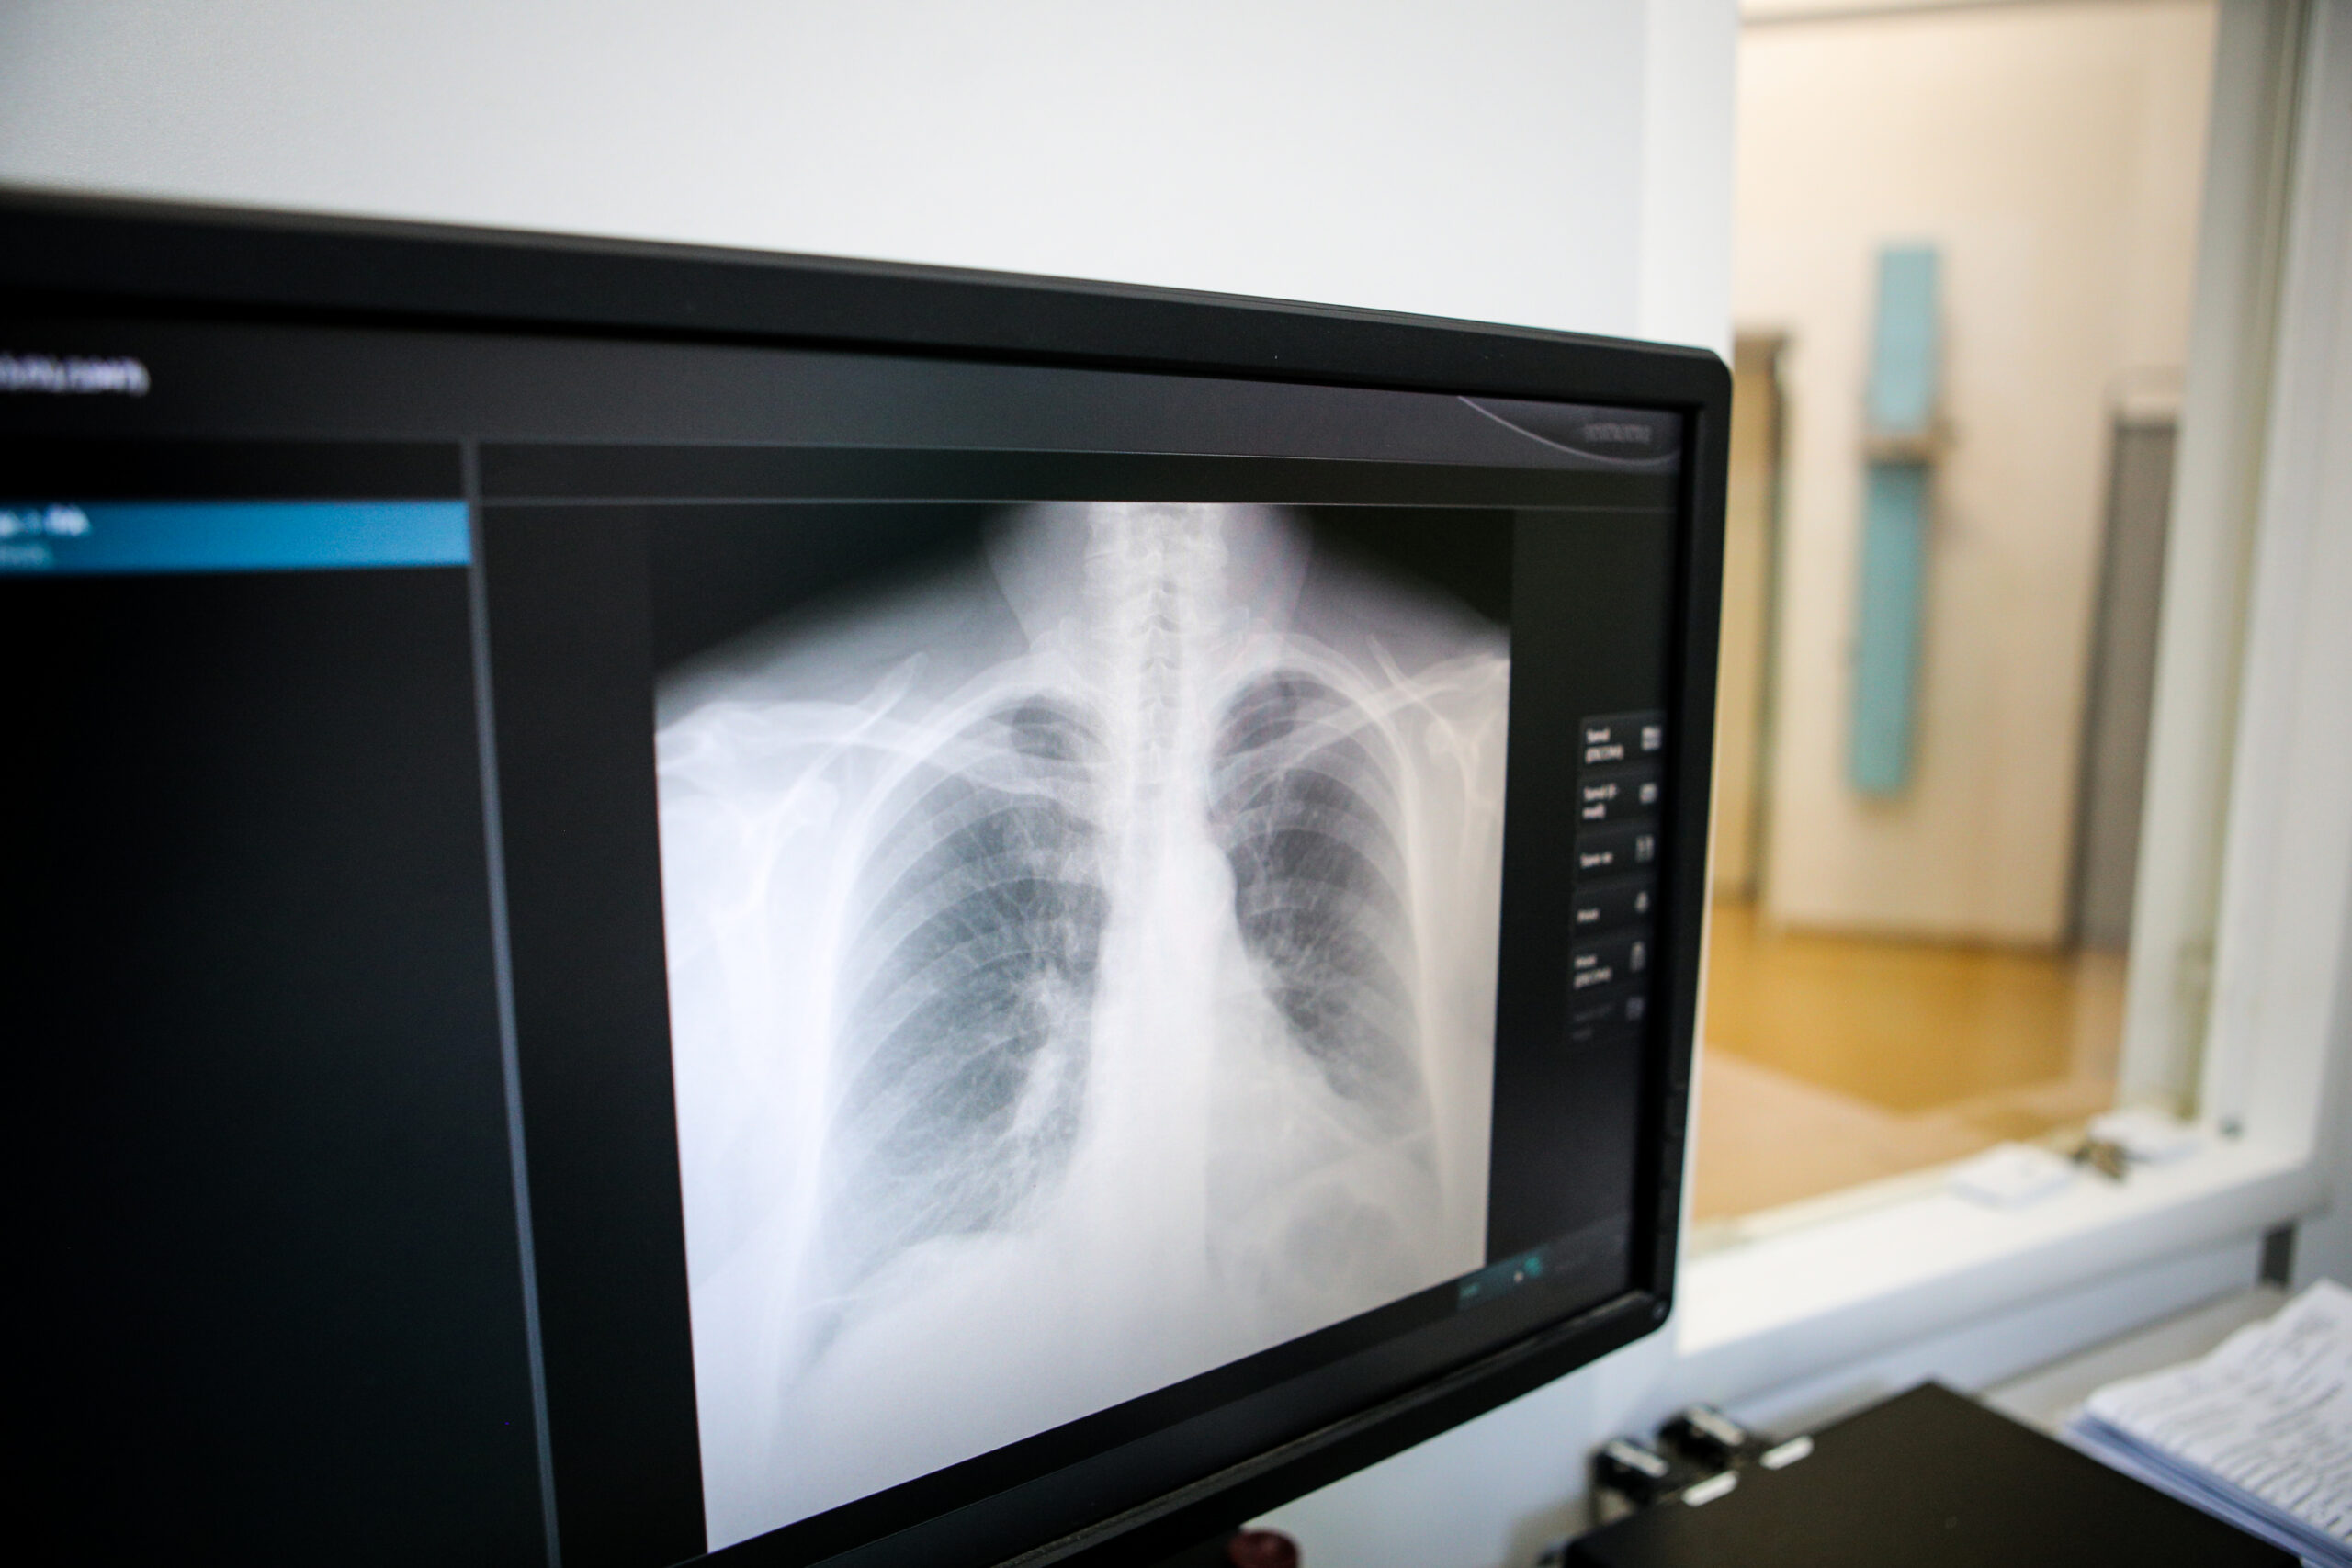

A lung nodule is a small area of dense tissue found in the lungs during lung cancer screenings or imaging tests using computed tomography (CT) scans or X-rays. Because symptoms are so rare, more than 90% of lung nodules are found by accident during a routine check-up, a chest X-ray, or a CT scan. These growths may look like a shadow or spot on the lung. A tumor measuring an inch or less is called a nodule (which is smaller than a mass.) If you have a nodule in your lungs, it’s called a pulmonary nodule. A nodule or mass may also be referred to as a neoplasm or lung nodule.

Lung nodules should always be further evaluated for cancer. Because lung cancer treatment is more effective when it’s caught early, monitoring lung nodules early could save your life. If you have a lung nodule, the next step is to get a CT scan to see if the nodule is growing over time. The time between scans might range anywhere from a few months to a year, depending on how likely the doctor thinks that the nodule could be cancer. This is based on the size, shape, and location of the nodule, as well as whether it appears to be solid or filled with fluid. If a repeat scan shows that the nodule has grown, your doctor might also want to get another type of imaging test called a positron emission tomography (PET) scan, which can often help tell if it is cancer. If later scans show that the nodule has grown or has other concerning features, your doctor will want to get a sample to check it for cancer cells.